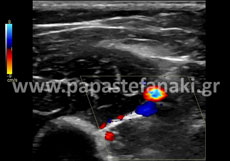

Triplex αγγείων

Για τα Triplex

• Καρωτίδων και σπονδυλικών αρτηριών

• Αρτηριών άνω και κάτω άκρων

• Φλεβών άνω και κάτω άκρων

• Οσχέου

Δεν απαιτείται προετοιμασία.